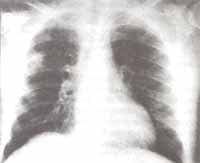

Hacia el cuarto día de hospitalización comenzó a presentar fiebre; tratando de definir un foco infeccioso diferente del intestinal, se le realizó radiografía de tórax que mostró infiltrados de ocupación alveolar localizados en el segmento posterior del lóbulo superior derecho con cavitación (Figura No. 1 y 2).

Figura No 1. Radiografía de tórax con opacidad en lóbulo superior derecho, mostrando cavitación.